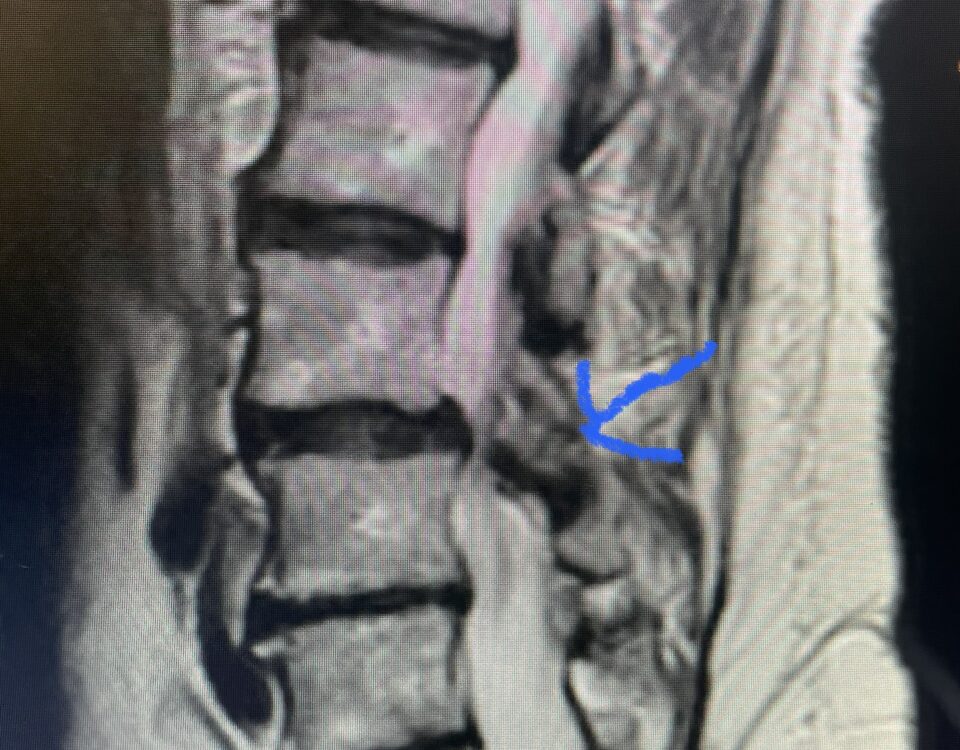

The spinal synovial cyst is one of the most interesting expressions of spinal instability. They emanate from the synovial lining of a degenerated facet joint that […]